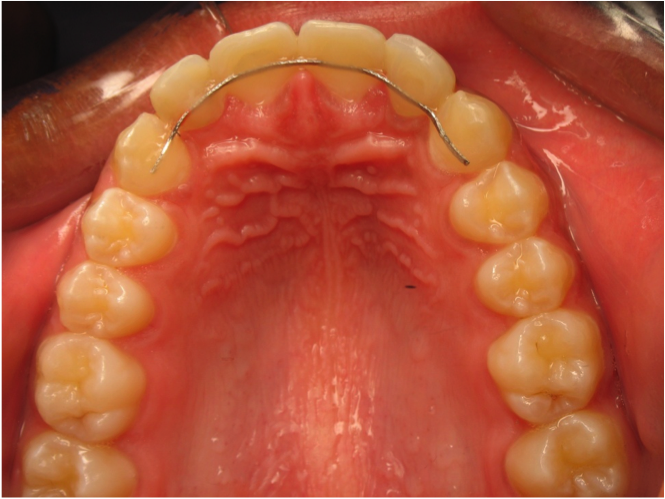

La contention

Cette période correspond à la conservation du résultat obtenu, l'orthodontiste demande au patient de porter un appareil de nuit ou colle un fin fil sur l'arrière des dents pendant une durée plus ou moins longue en fonction de la tendance à la récidive (tendance au retour à l’état antérieur) qui est très variable selon les personnes et les malformations. Cette phase est trop souvent négligée par les patients qui est pourtant essentielle pour la pérennité du résultat. Le vieillissement de la denture s’accompagnant quelquefois de modifications de la position des dents, le patient doit rester vigilant et ne pas omettre les visites annuelles de contrôle chez son praticien traitant.